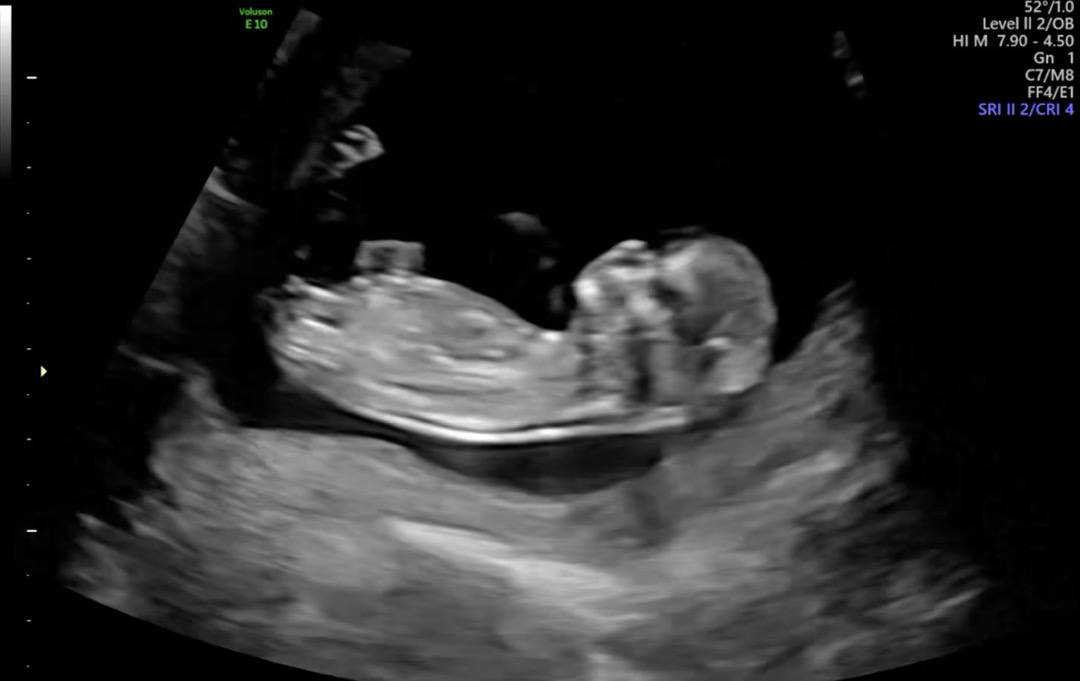

12주 각도법 봐주세요~~

12주차에요! 딸일까요 아들일까요!?🥸🥸